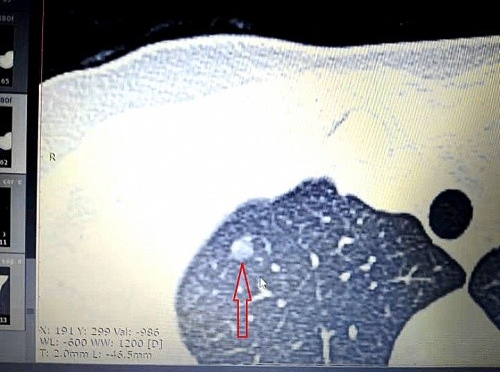

肺结节包括磨玻璃结节、部分实性结节即混合磨玻璃结节,以及实性结节三种。直径3—20mm结节、持续存在超过3个月以上的磨玻璃结节发展为肿瘤的概率是59%,而实质性结节仅为11%。磨玻璃结节切除后10年生存率为100%,而部分实性结节或实性结节的肿瘤多为侵袭性强或增长较快的微浸润腺癌或浸润性腺癌,切除后10年生存率仅为40-80%。从恶性比例看,磨玻璃结节危害更大;而从预后看,实性结节更危险。